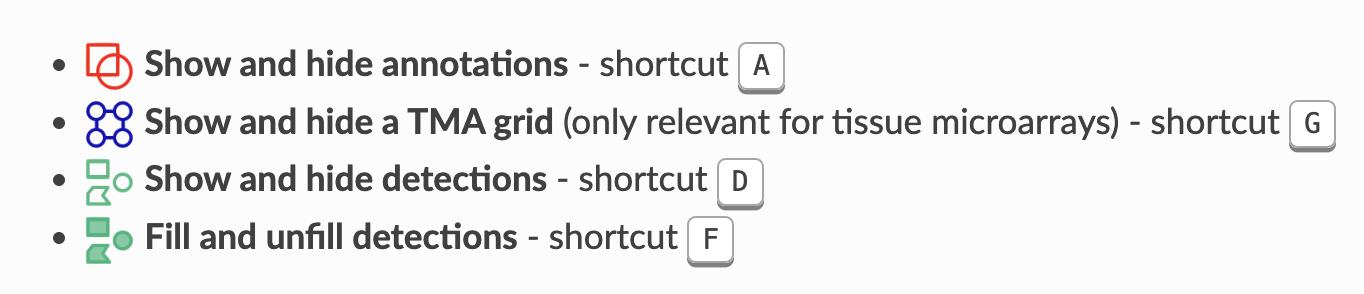

2-10:显示与隐藏

随着图像上对象数量的增加,可能会变得杂乱或令人困惑。有四个有用的工具栏按钮可以帮助自定义对象如何显示。

这些按钮允许您快速切换显示标记,以在查看分析数据和底层图像之间切换。

您还可以在图像上右键点击,进一步修改细胞显示的方式,即是否显示核或边界。